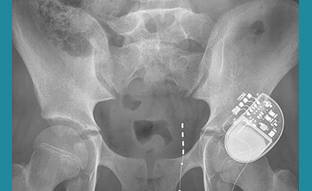

- Sacral Nerve Stimulation

- Sacral Nerve Stimulation Clinic